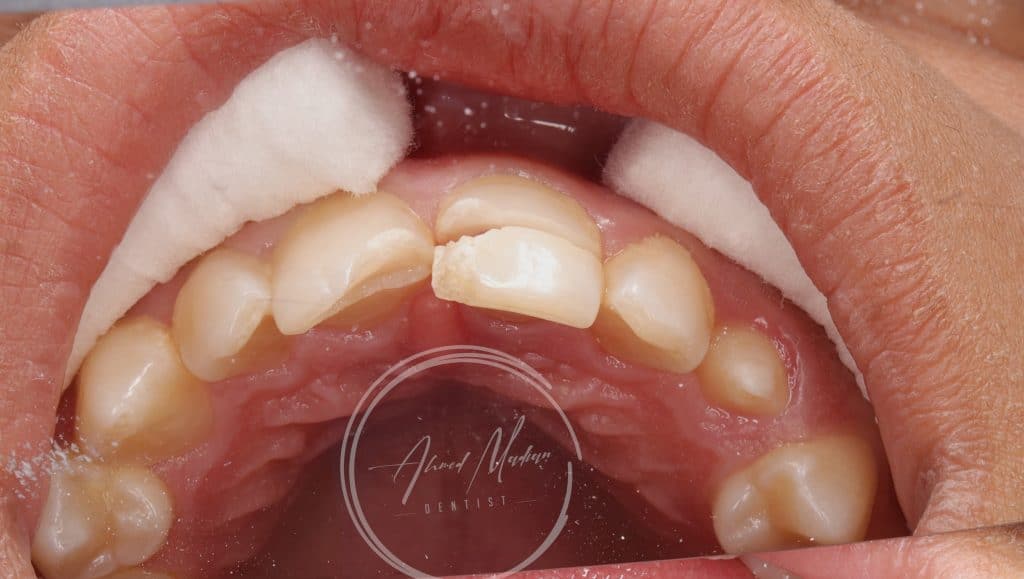

14 y male patient came to the office complaining of trauma in the anterior region

After clinical and radiographic examination , senstivity , mobility assessment

Tooth no 11 showed complicated crown root fracture , exposed pulp , closed apex

Tooth no 12 uncomplicated corwn fracture , class lV